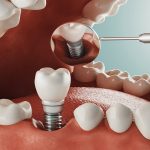

Dentist That Do Implants Near Me

Visiting a dentist that do implants near me requires an adequate preparation so that you will be able to get the best result. Call our Dental implants dentist in Houston.

Visiting a dentist that do implants near me requires an adequate preparation so that you will be able to get the best result. Call our Dental implants dentist in Houston.